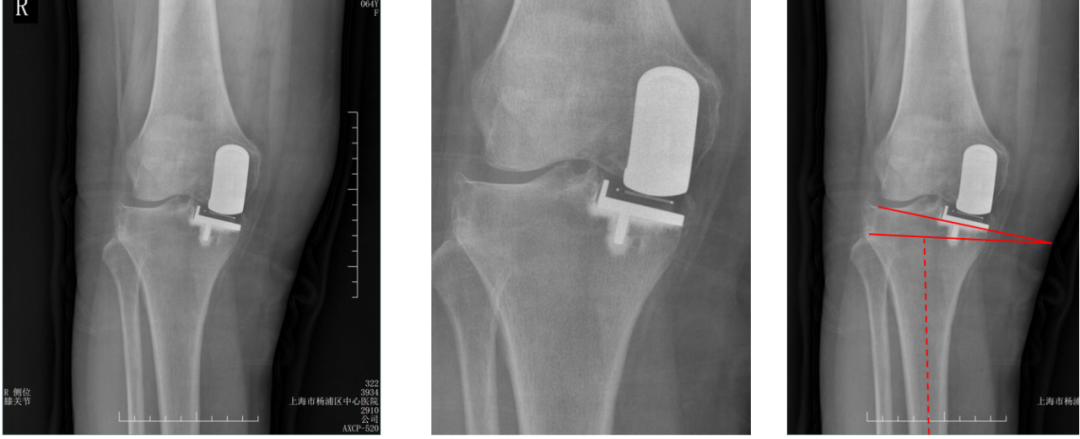

病例1:胫骨假体后倾角度>7°

问题:胫骨假体后倾角度12°,轻度膝外翻

病例1:胫骨假体翻修

UKA to UKA 更换胫骨假体